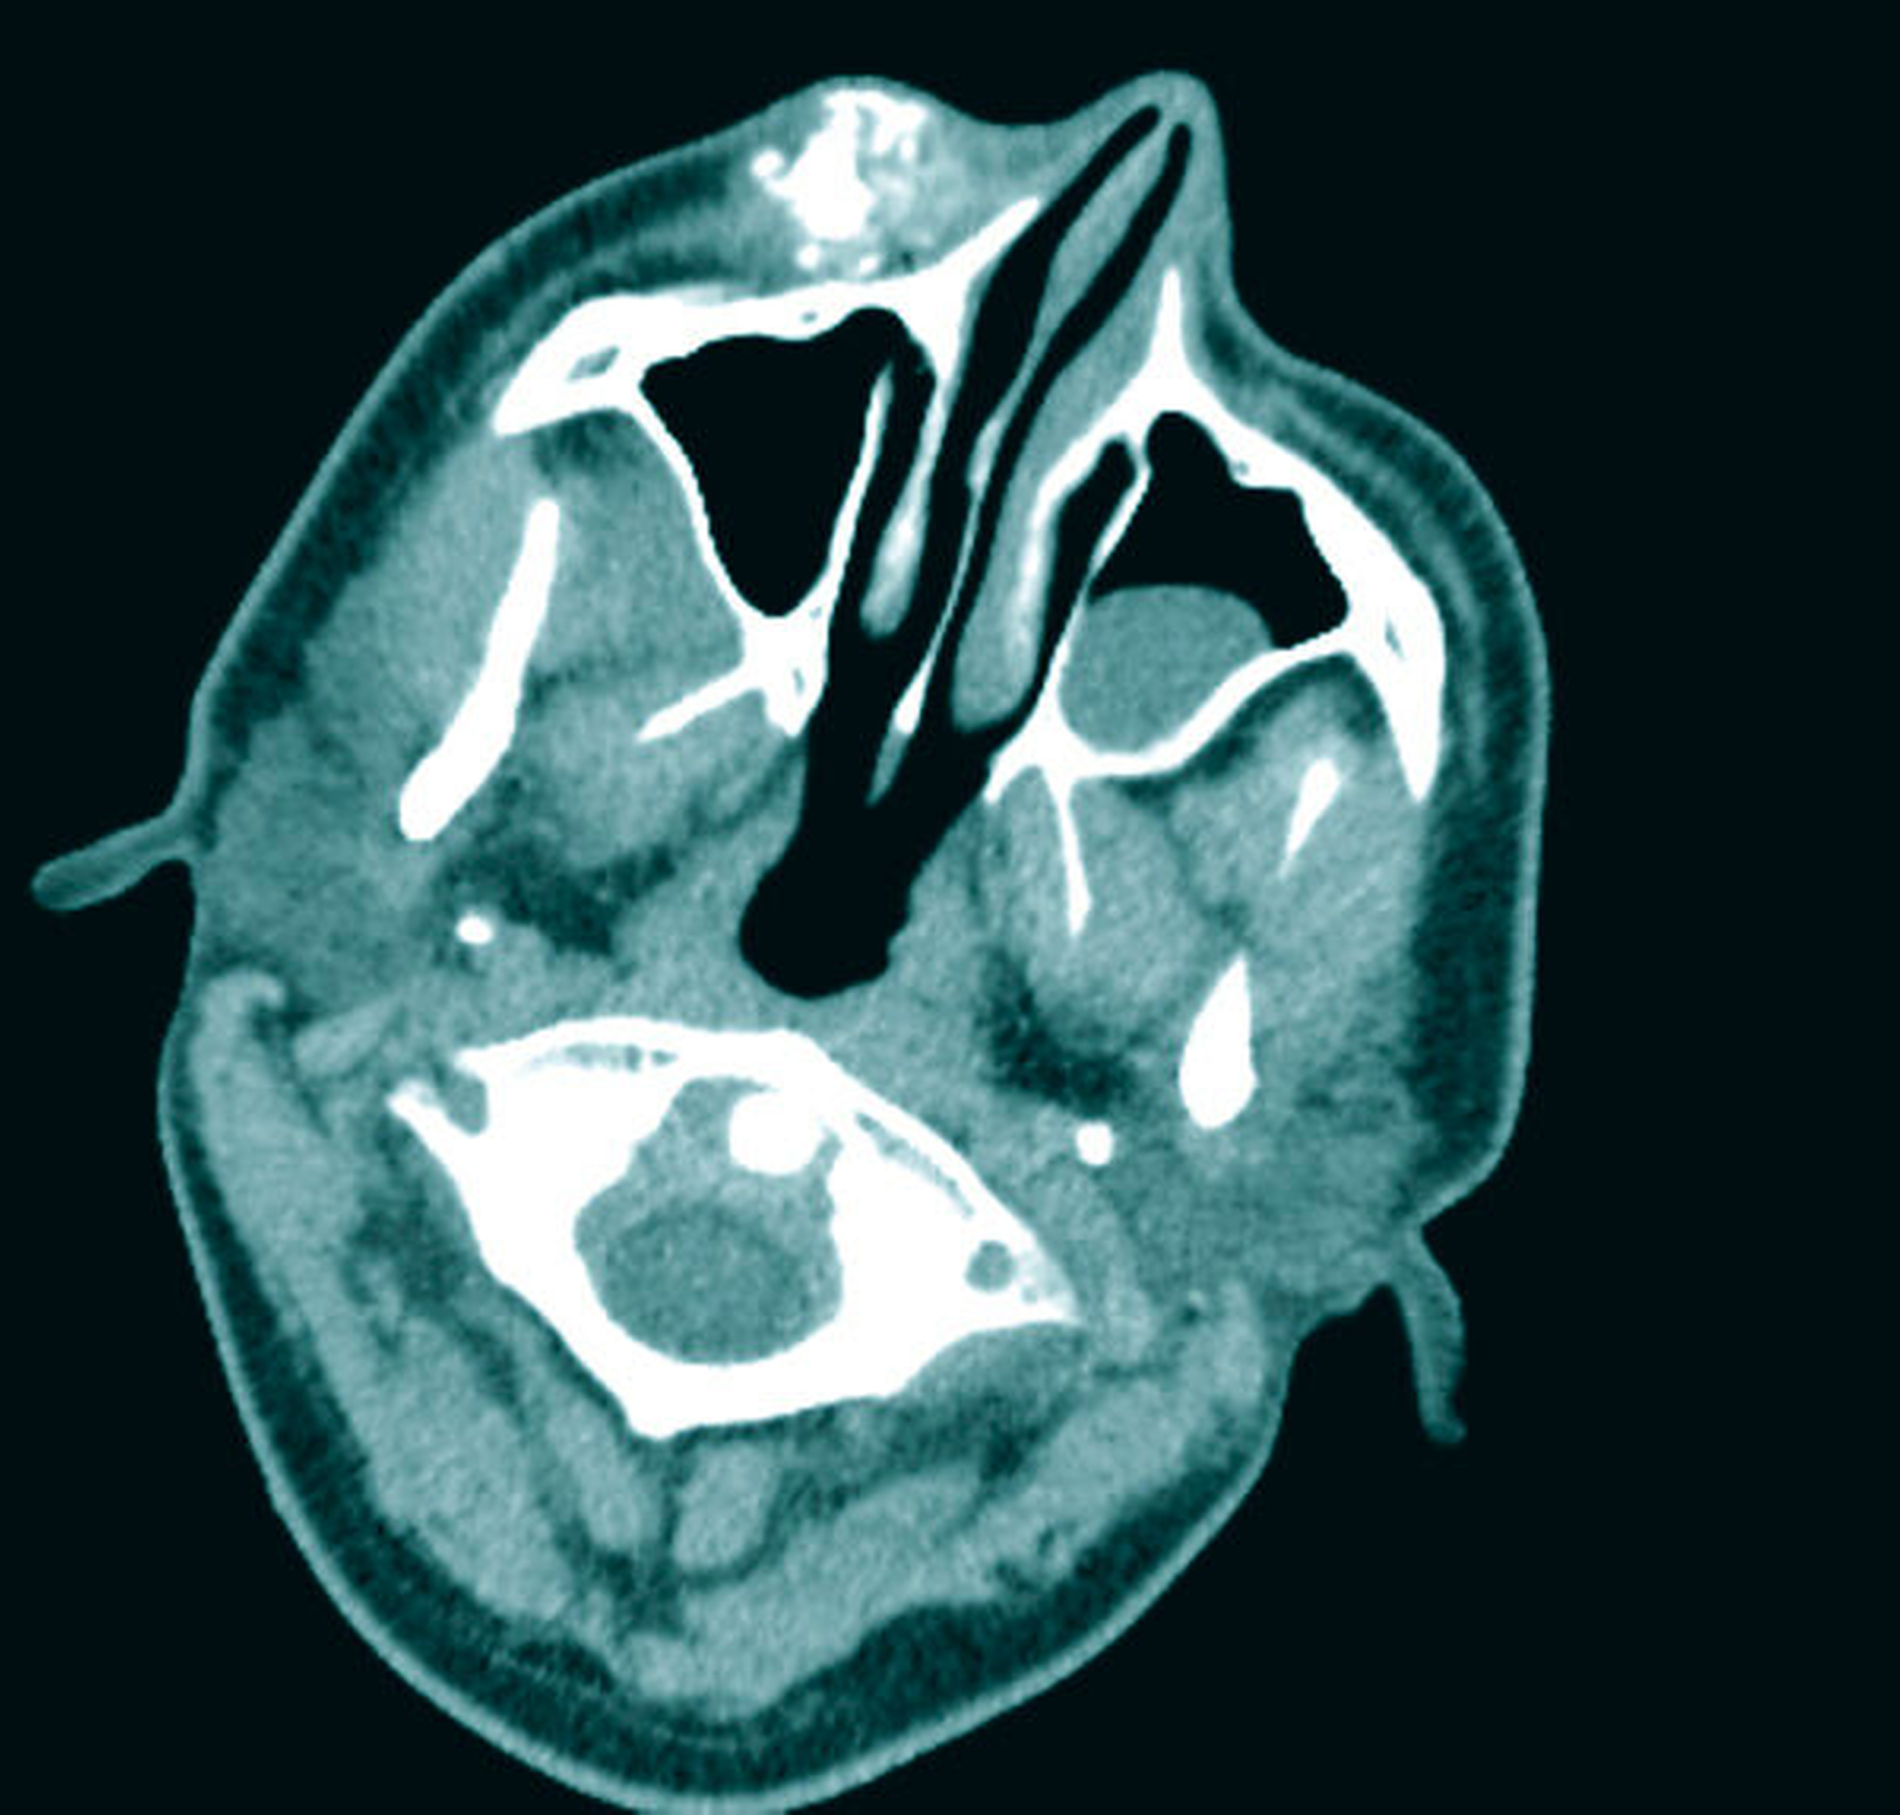

Zur Beurteilung der Befundausdehnung und zur Planung der Therapie wurde präoperativ eine Magnetresonanztomografie (MRT) des Schädels angefertigt (Abbildung 2). Hier zeigte sich die bekannte vaskuläre Malformation der rechten Wange mit Ausläufern nach intraorbital, in die Fossa pterygopalatina und infratemporalis. Im Vergleich zu den Voraufnahmen zeigte sich eine geringe Größenprogredienz des extraorbitalen Befunds (Abbildung 3).

Nach präoperativer Sklerosierung des Wangenhauptbefunds (Abbildung 4) erfolgte am Folgetag die Resektion in Intubationsnarkose. Hierzu wurde nach subziliärer Schnittführung (Abbildung 5) eine scharfe Präparation des Tumors nach kaudal unter Schonung des Ramus buccalis des Nervus facialis durchgeführt (Abbildung 6) und dieser schließlich exzidiert (Abbildung 7). In der histopathologischen Aufarbeitung zeigten sich Muskel-, Fett- und Weichgewebe mit reichlich interponierten, kavernös konfluierenden, blutgefüllten Gefäßformationen unterschiedlicher Größe (Abbildung 8). Der postoperative Verlauf gestaltete sich bis auf eine vorübergehende Einschränkung der Fazialisfunktion im Bereich des Mundastes unauffällig, sodass der Patient zeitnah in die ambulante Weiterbetreuung entlassen werden konnte.